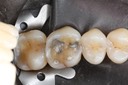

Kyle Chock #18 caries removal